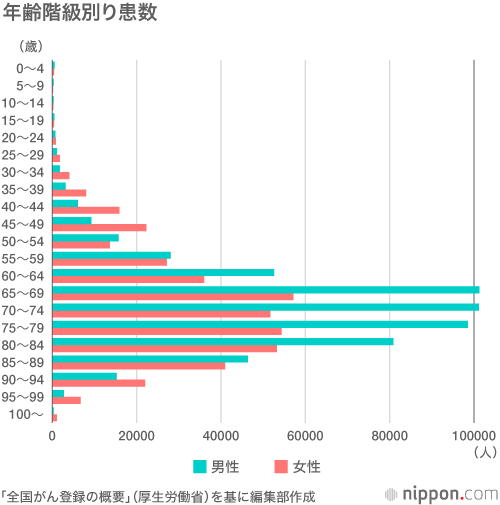

年齢別では、65歳以上が全体の73.7%を占める。特に、男性は65歳以降急激に増えるのが特徴的だ。女性も60歳代から70歳代にかけて患者数が増えるものの、男性に比べると増え方はなだらかだ。